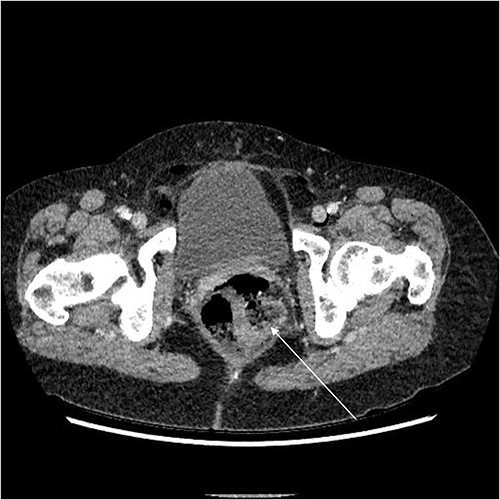

A chest X-ray confirmed subcutaneous emphysema and pneumoperitoneum and no pneumothorax (Fig. 1). Subsequent computed tomography (CT) of the abdomen and pelvis revealed extensive extraluminal gas throughout neck, torso and upper limbs including retroperitoneal, intraperitoneal, mediastinum, anterior and posterior chest wall, superficial and deep layers of the neck, right lower abdominal wall and bilateral inguinal canals (Figs 2 and 3).

Axial CT showing extensive intra- and extraperitoneal free gas.